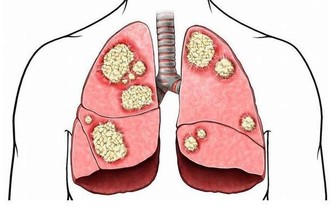

三是補養肺腎。中醫認為,按五行規律,夏天心火旺而肺金、腎水虛衰,要注意補養肺腎之陰。可選用枸杞子、生地、百合、桑葚以及酸收肺氣藥,如五味子等,可防出汗太過,耗傷津氣。